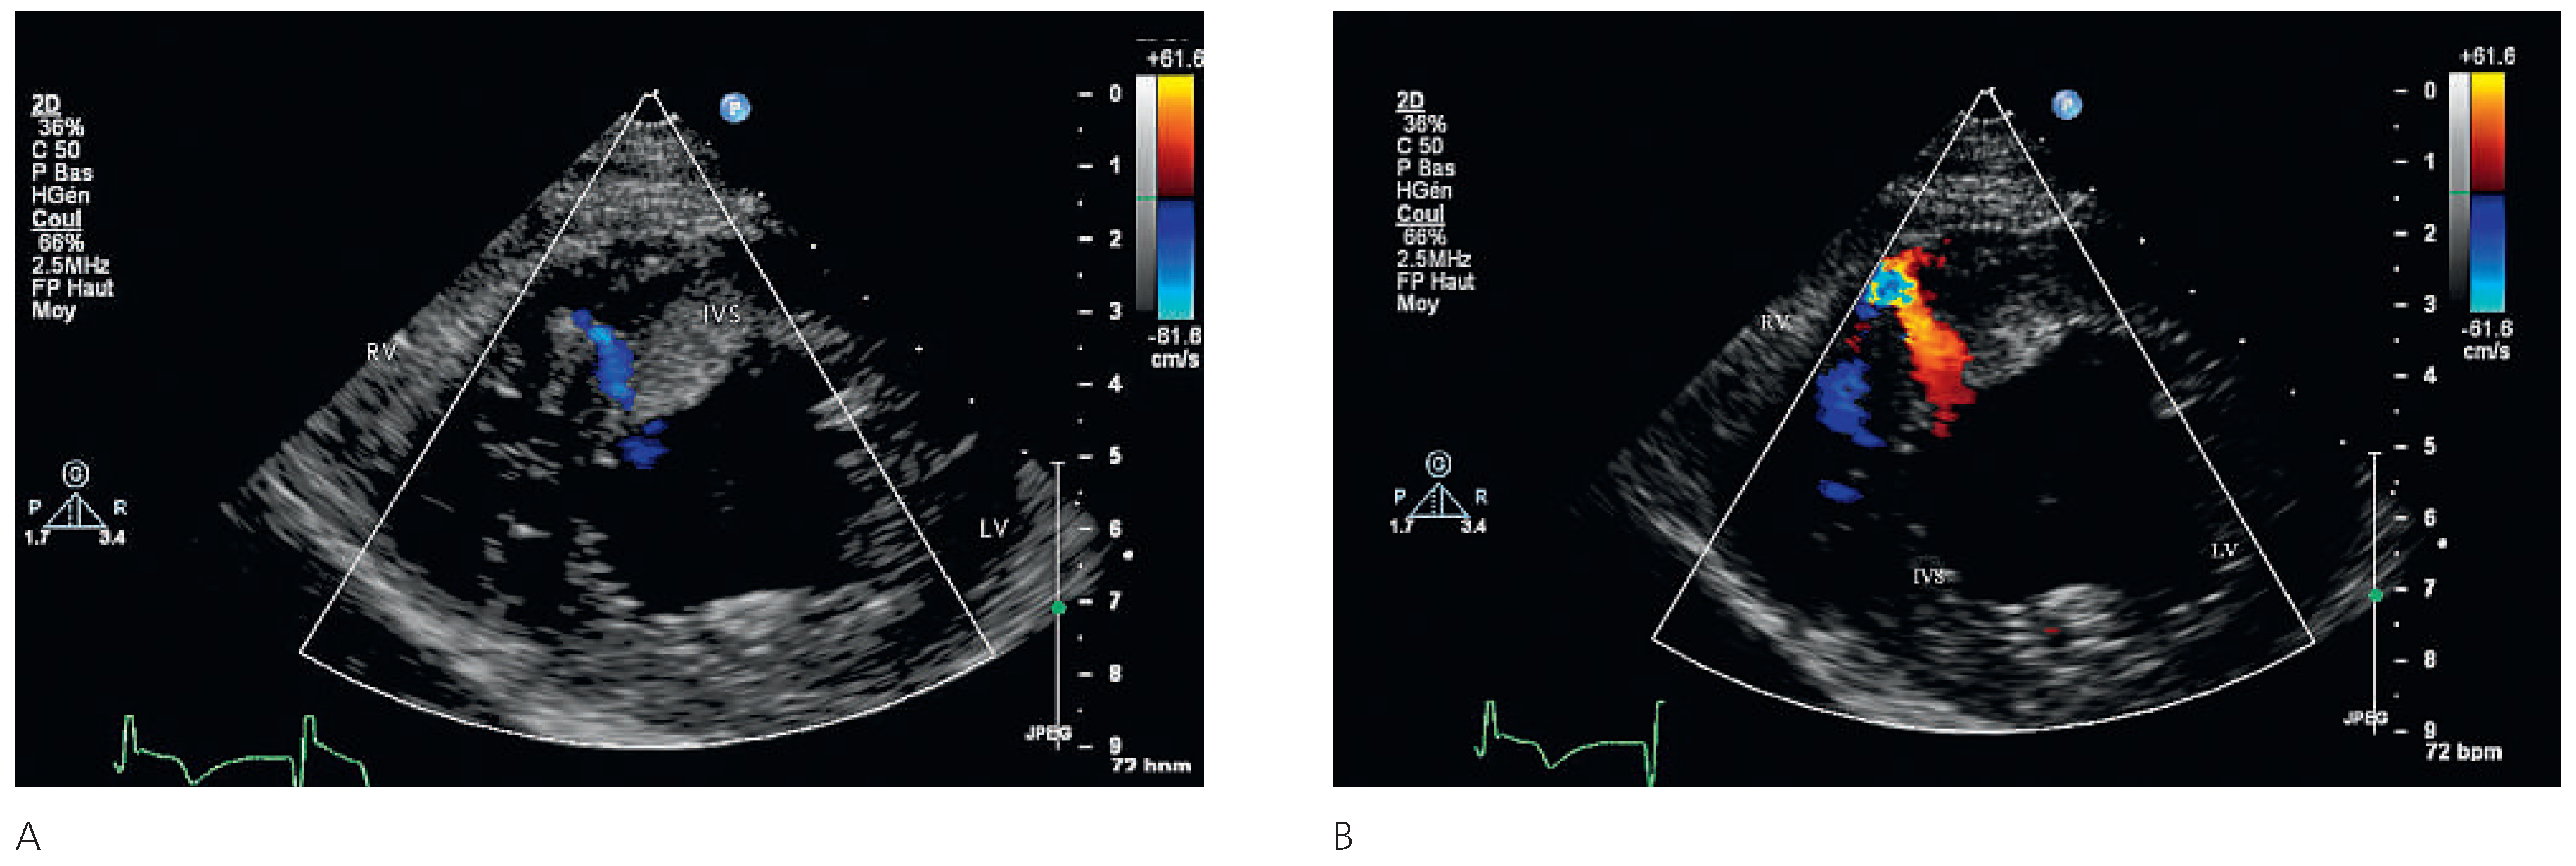

A 87-year-old female patient was hospitalised for decline in general health status, fatigue and oedema following a fall two weeks earlier. On no occasion did the patient experience chest pain or shortness of breath. The blood pressure and heart rate on admission were 113/79 mm and 80 bpm Hg respectively. Cardiopulmonary auscultation revealed a harsh, loud holosystolic murmur most audible along the left sternal border and radiating to the base, apex and right parasternal area, with accentuation of the second heart sound and crepitus rales across all lung fields. Bilateral ankle oedema was present without distention of the jugular veins. The ECG was compatible with subacute anterior and inferior myocardial infarction. Echocardiography showed severely depressed left ventricular function in the presence of apical and anteroseptal dyskinesia and septal rupture with bidirectional shunt on colour Doppler. In addition, an apical thrombus and severe aortic stenosis with severe pulmonary hypertension were noted. In light of the patient’s age and the echocardiographic findings it was decided not to institute active treatment, and during the echocardiographic examination the patient developed profound cardiogenic shock and died.

Figure 3. Parasternal short axis showing bidirectional shunt: right to left shunt (A), left to right shunt (B). LV = left ventricle; IVS = interventricular septum; RV = right ventricle.